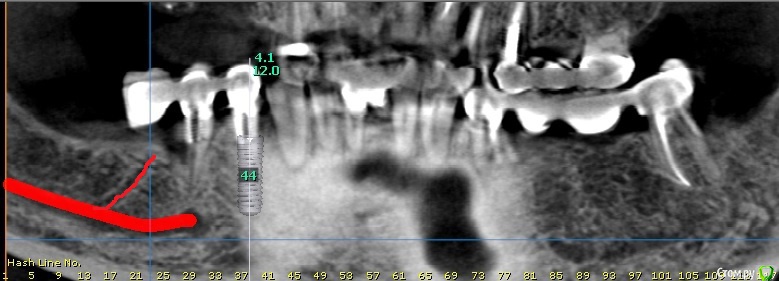

bilal Опубликовано 20 мая, 2019 Поделиться Опубликовано 20 мая, 2019 Подскажите, будут ли последствия, если я поставлю имплант в области 46. Смущает ответвление от основного канала, Ссылка на комментарий

колесников Опубликовано 21 мая, 2019 Поделиться Опубликовано 21 мая, 2019 Все на своих местах,правильно делаете что опасаетесь. Возможно ничего не будет,а могут быть боли невралгического характера и апекальный остеонекроз,если вовремя не убрать имплант. Лучше ставить в 2 этапа,от греха подальше.как говорится 1 Ссылка на комментарий

bilal Опубликовано 23 мая, 2019 Автор Поделиться Опубликовано 23 мая, 2019 (изменено) как по мне так это костный рисунок такой покажите ответвление выколи глаз, не вижу может и костный канал.импланты поставил, полет нормольный. Изменено 23 мая, 2019 пользователем bilal 2 Ссылка на комментарий

___49___ Опубликовано 23 мая, 2019 Поделиться Опубликовано 23 мая, 2019 (изменено) Все на своих местах,правильно делаете что опасаетесь. Возможно ничего не будет,а могут быть боли невралгического характера и апекальный остеонекроз,если вовремя не убрать имплант. Лучше ставить в 2 этапа,от греха подальше.как говорится+100, фото показательно Изменено 23 мая, 2019 пользователем ___49___ Ссылка на комментарий